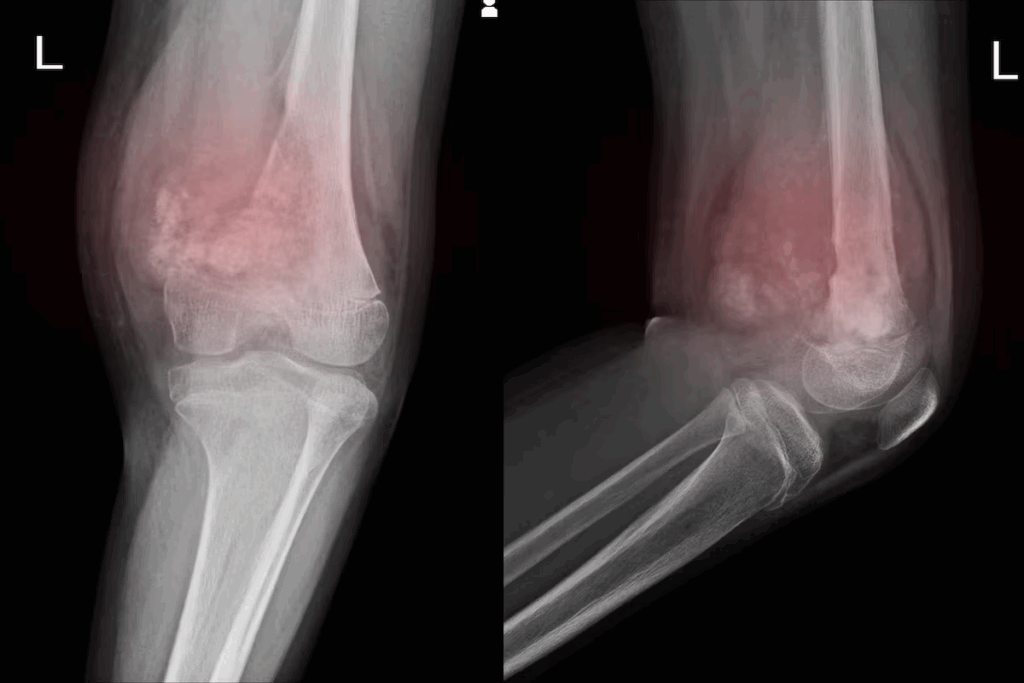

Detecting Leukemia in Bone Marrow and Blood

Diagnosing leukemia means finding abnormal cells in bone marrow and blood. A bone marrow biopsy and aspiration are key steps. These tests show the leukemia type and how far it has spread.

Bone Marrow Biopsy and Aspiration

A bone marrow biopsy takes a small bone marrow sample for tests. Aspiration gets a liquid bone marrow sample. Both give important info on leukemia cells.